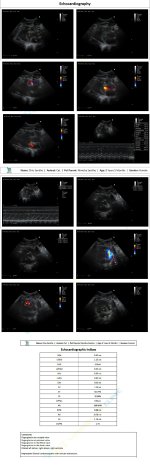

Yesterday was the x-ray which still showed congestion. We did a 2d echo (scans attached). Vet said stuff like HCM, regurgitation, dilation. I had briefly read about HCM and got overwhelmed and didn't ask the vet for more details. But she sent me off with 30 days medicines (long list of meds below) and we'll do a repeat 2d echo after a month. ETA: she lost about 0.5 kg in the last 15 days.